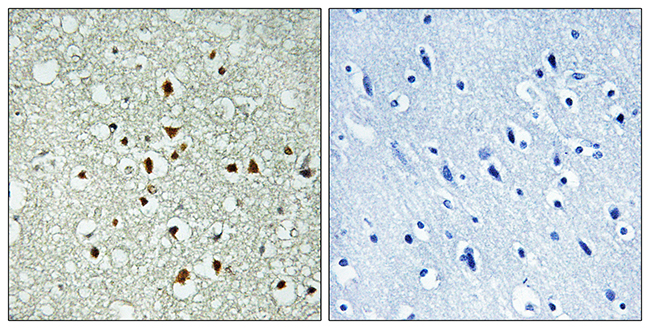

Anti-Fos AntibodyA98315

ApplicationsELISA, ImmunoHistoChemistry

ReactivityHuman, Mouse, Rat

- SizePrice